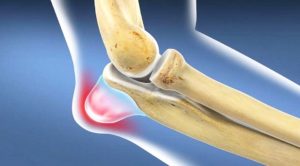

Бурсит локтевого отростка (БЛО) – это состояние, при котором воспаляется синовиальная сумка, примыкающая к локтевому отростку локтевой кости.

Поверхностное положение синовиальной сумки, а именно между локтевым отростком локтевой кости и кожей, чувствительно к воспалениям, возникающим из-за ряда причин, в первую очередь, из-за острой или повторяющейся травм.

- Классическим проявлением воспаления синовиальной сумки является отек задней части локтя. Эта отечность ясно выделяется внешним видом, т.к. похожа на гусиное яйцо, «выросшее» на кончике локтя.

Патология представляет собой воспаление синовиальной сумки локтя, располагающейся на разгибательной поверхности. Патология охватывает бурсу – мешок, который находится под кожей выше локтевого отростка.

Задача бурсы заключается в обеспечении плавного и мягкого скольжения костей и сухожилий мышц плеча. При воспалении трение между этими участками усиливается, поэтому развивается воспаление.